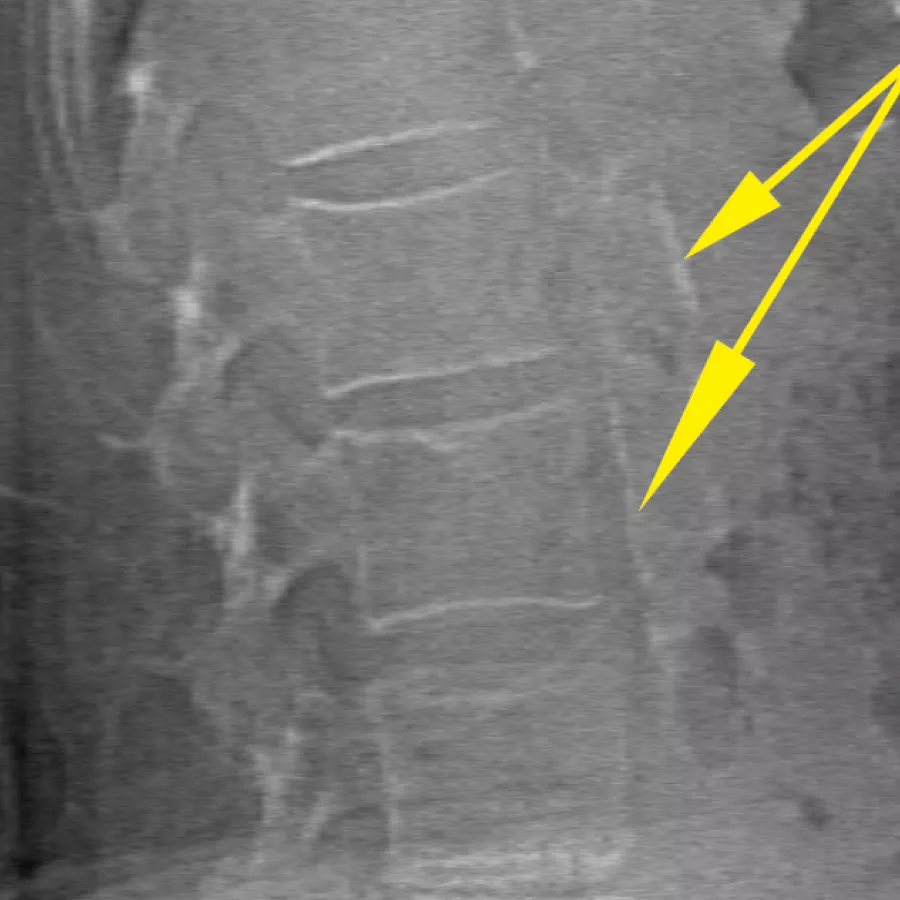

Clinical Images

Horizon DXA produces radiographic quality images of the entire femur for assessment of potential atypical femur fractures.31 A quick, 15-second scan reveals cortical thickening of the bone, making it fast and easy to monitor the effects of bisphosphonate therapy over time.

Visualise calcified plaque in the abdominal aorta, which may be a significant indication of heart disease and stroke, two of the leading causes of death in men and women.

Assess fracture risk by combining an accurate measurement of bone density with high-resolution vertebral imaging. You can identify spine fractures with a low-dose, single-energy image in 10 seconds.

Improve accuracy and reduce post-exam analysis errors with precise, software-assisted placement of inter-vertebral disc spaces for graphic analysis.